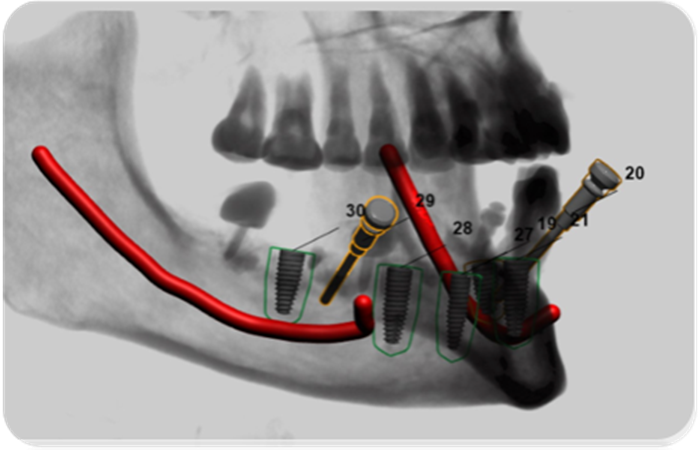

數(shù)字化微創(chuàng)種植修復(fù)

硬件設(shè)備:配有業(yè)內(nèi)先進的NewTom口腔CBCT、口腔X線數(shù)碼全景機、瑞士Straumann及韓國奧齒泰牙種植系統(tǒng)、種植支抗植入系統(tǒng)、超聲骨刀切割系統(tǒng)、FOTONA激光口腔治療儀、顯微根管治療系統(tǒng)、CAD/CAM椅旁修復(fù)系統(tǒng)、數(shù)字化掃描系統(tǒng)、STA口腔無痛局麻儀、舒適化鎮(zhèn)靜麻醉等一系列高端??浦委熢O(shè)備。